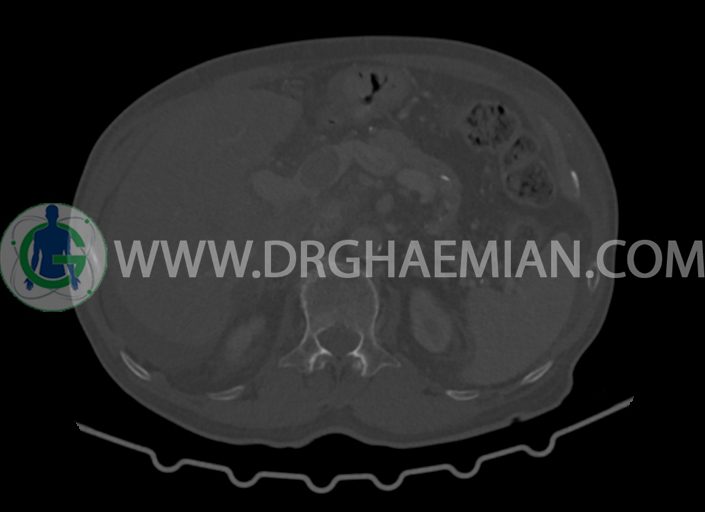

در سی تی اسکن اسپیرال شکم و لگن با کنتراست خوراکی و وریدی (مولتی دیدکتور 16 با مقاطع ظریف و بازسازی های ساژیتال و کرونال) :

-کیست های کورتیکال ساده در هر دو کلیه به بزرگترین قطر 27mm در سمت چپ (بوسنیاک 1)

-لنف نودهای متعدد بعضا با مرکز نکروزه به شرح زیر رویت شد:

-به بزرگترین SAD=14mm در گاستروهپاتیک

-به SAD=10mm در زنجیره سلیاک

-چند لنف نود به بزرگترین SAD=16mm در محور SMA

-توده ی بزرگ با حدود لبوله به ابعاد 89x87x76mm در لوب چپ کبد همراه با گسترش اکستراکپسولار و

شواهد آتروفی لوب جپ کبد

-توده به قطر 33mm در سگمان 6 کبد

-توده ی هیپودنس به ابعاد 30x21mm در ورید پورت خارج کبدی مطرح کننده ی Tumor thrombosis

در ارتباط با ضایعات کبدی در درجه ی اول متاستاز مطرح است. در تشخیص افتراقی با توجه به آتروفی لوب

چپ، mass forming cholangiocarcinoma نیز مطرح می گردد.